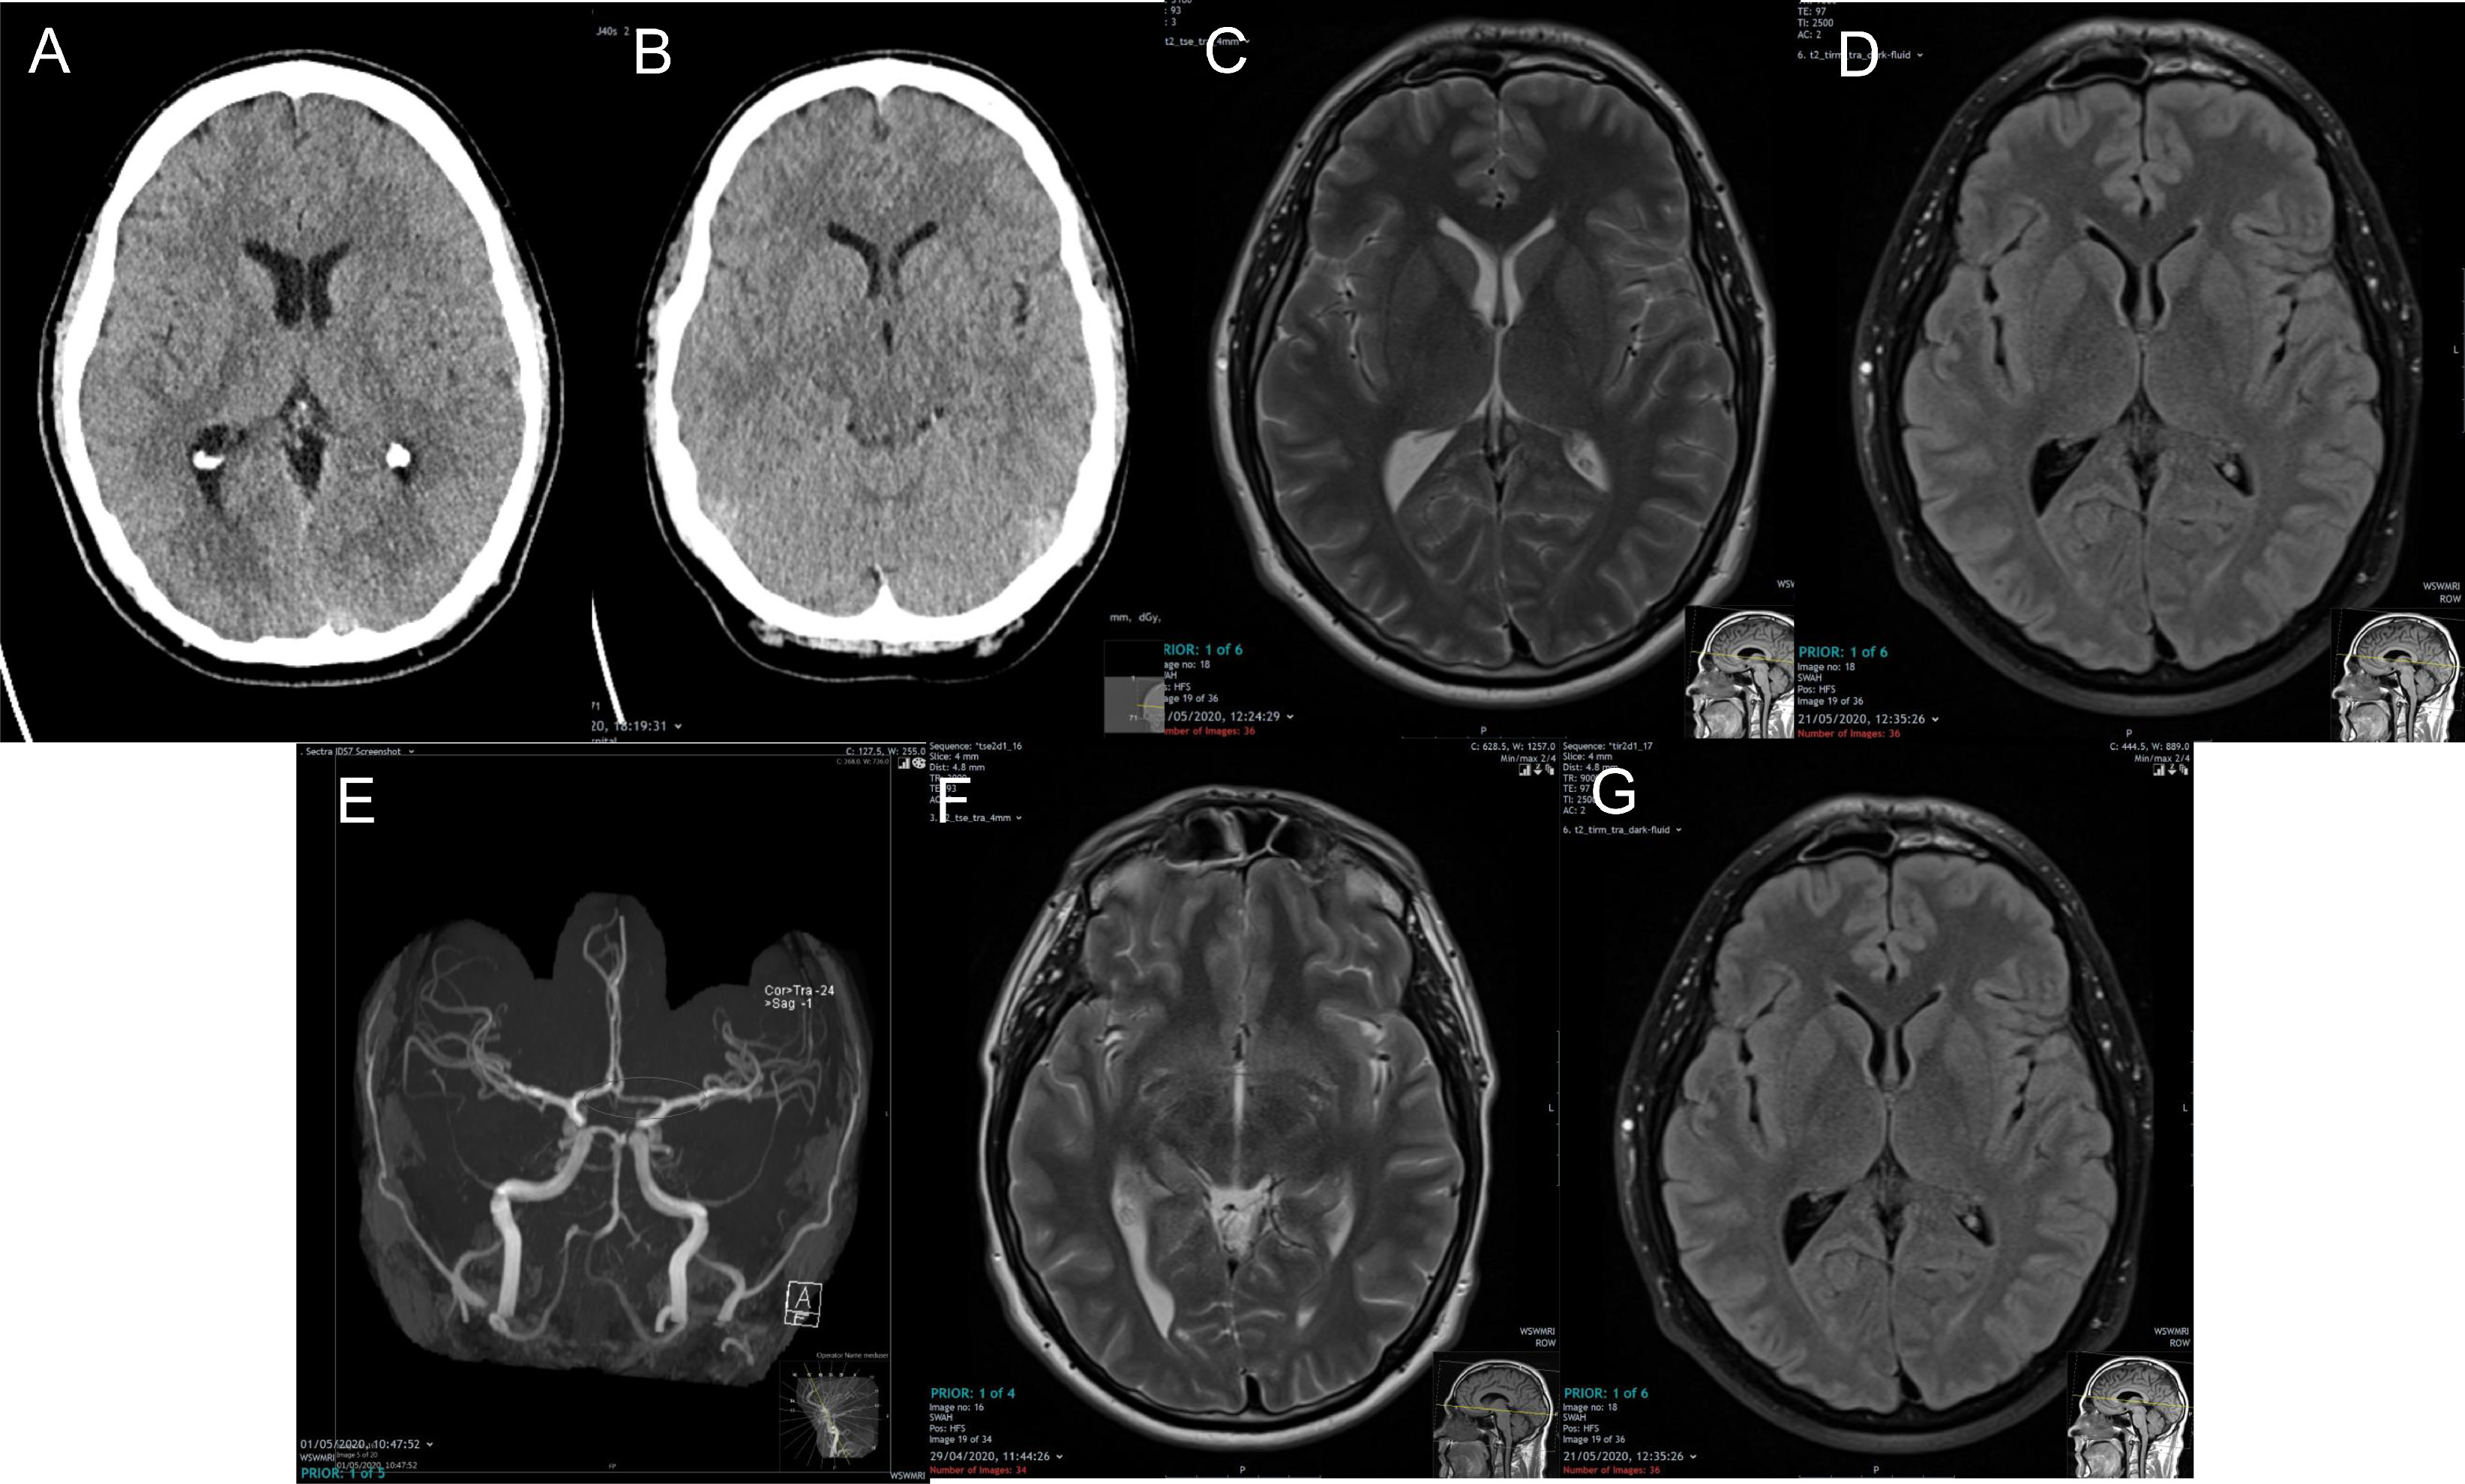

Il titolo del lavoro è : A Case Report: Multifocal Necrotizing Encephalitis and Myocarditis after BNT162b2 mRNA Vaccination against COVID-19

" Il presente report presenta il caso di un uomo di 76 anni con malattia diParkinson (PD) morto tre settimane dopo aver ricevuto la sua terza vaccinazione COVID-19. Il paziente è stato vaccinato per la prima volta a maggio 2021 con il vaccino a vettore virale ChAdOx1 nCov-19, seguito da due dosi del vaccino a RNAm BNT162b2 a luglio e dicembre 2021. La famiglia del defunto ha richiesto un'autopsia a causa di segni clinici ambigui prima della morte. La malattia di Parkinson è stata confermata dagli esami post mortem. Inoltre, erano evidenti segni di polmonite da aspirazione e arteriosclerosi sistemica. Tuttavia, le analisi istopatologiche del cervello hanno portato alla luce reperti precedentemente insospettati, tra cui vasculite acuta (prevalentemente linfocitaria) e encefalite necrotizzante multifocale di eziologia sconosciuta con infiammazione pronunciata inclusa reazione gliale e linfocitica. Nel cuore erano presenti segni di cardiomiopatia cronica, miocardite e vasculite linfo-istiocitica acuta lieve. Sebbene non ci fosse una storia di COVID-19 per questo paziente, è stata eseguita l'immunoistochimica per gli antigeni SARS-CoV-2 (proteine spike e nucleocapside). Sorprendentemente, è stato possibile rilevare solo la proteina spike ma nessuna proteina nucleocapside all'interno dei focolai di infiammazione sia nel cervello che nel cuore, in particolare nelle cellule endoteliali dei piccoli vasi sanguigni. Poiché non è stato possibile rilevare alcuna proteina nucleocapside, la presenza della proteina spike deve essere attribuita esclusivamente al vaccino a Rnam piuttosto che all'infezione virale da Covid. I risultati di questo studio confermano precedenti segnalazioni di encefaliti e miocarditi associate ai vaccini COVID-19 basati sulla tecnologia a Rna messaggero.